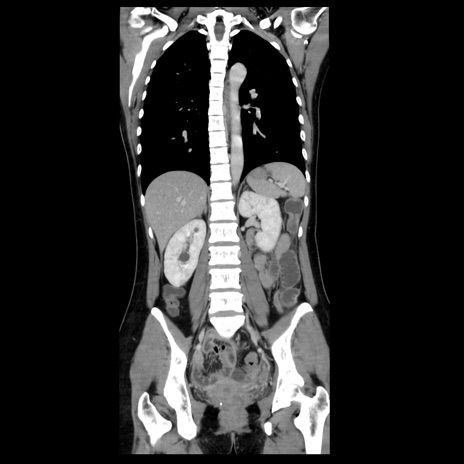

症例39(冠状断像)

【症例】40歳代女性

【主訴】上下腹部痛

【現病歴】2日目から下腹部痛あり。夜間は痛みで眠れなかった。昨日より上腹部痛と下痢が出現。臥位で痛みは軽快したため、休んでいた。本日になって臥位でも立位でも痛みが強くなってきたため救急要請。

【既往歴】子宮内膜症

【身体所見】部:平坦・軟、左上下腹部に圧痛あり、反跳痛あり。

【データ】WBC 21800、CRP 26.78

CT